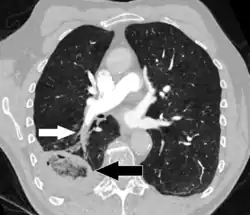

CT scan of a lung infarction because of chronic pulmonary embolism (white arrow). The infarcted area (black arrow) has a reverse halo sign.